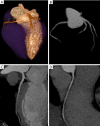

Case of false positive displaying intrastent restenosis at cardiac computed tomography (CCT). (A) Volume rendering; (B) multiplanar reconstruction of the left anterior descending coronary artery; (C) corresponding conventional angiogram depicting intrastent patency.

Multiplanar reconstructions of the right coronary artery displaying calcified plaques with smooth (A) and sharp filtering (B).